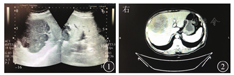

血白细胞计数为7.73×109/L,中性粒细胞占比为0.844,中性粒细胞计数为6.52×109/L,红细胞计数为2.55×1012/L,血红蛋白为71.0 g/L,血小板计数为274×109/L。CRP为102.09 mg/L,降钙素原为0.16 μg/L,ESR为110 mm/1 h。凝血功能:PT为12.7 s,纤维蛋白酶原(fibrinogen,FIB)为5.72 g/L。肝功能:ALT为7 U/L,AST为19 U/L,GGT为119 U/L,白蛋白为30.8 g/L,TBil为5.0 μmol/L。心肌酶:肌酸激酶(creatine kinase)为9.0 U/L,肌酸激酶同工酶(creatine kinase isoenzyme,CK-MB)为14 U/L。肾功能:尿素氮为5.7 mmol/L,肌酐为48 μmol/L。HIV抗体及确证试验均(+),HIV RNA为5.4×103 IU/mL,巨细胞病毒(cytomegalovirus,CMV)<400拷贝/mL,梅毒螺旋体抗体、HBV表面抗原和丙型肝炎病毒抗体均阴性。腹部多普勒超声检查(图1)显示:肝内可见不均质、多发、低回声团块,最大者约126 mm×98 mm,与周边分界欠清,形态欠规整,考虑肝脓肿?腹部CT检查(图2)显示:肝内多发结节及团块稍低密度影,较大者范围约12.8 cm×10.2 cm,病灶边界显示不清。考虑肝脓肿?淋巴瘤?